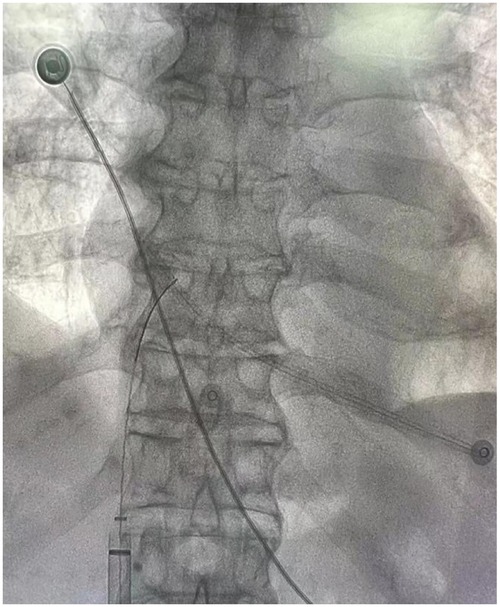

Background: With the advancements in endovascular techniques, reports of rare vascular complications have increased. This case describes the accidental fracture of a non-cuffed hemodialysis catheter and its subsequent endovascular management, offering valuable insights for the treatment of similar intravascular foreign bodies (IFBs). Case Report: An 83-year-old male with a non-cuffed catheter presented after a catheter fracture. Radiographic imaging confirmed migration of the fragment to the right atrium. After a multispecialistic collaboration assessment, endovascular retrieval was performed via right femoral access using a filter retrieval device under fluoroscopic guidance. The catheter fragment was successfully captured and removed without procedural complications. The patient recovered uneventfully and remained well at follow-up evaluations. Conclusion: This case highlights the efficacy and safety of percutaneous endovascular retrieval for managing IFBs, providing a minimally invasive alternative to surgery with high success rates. Meticulous catheter handling and regular integrity assessments are critical to prevent and promptly manage such events.